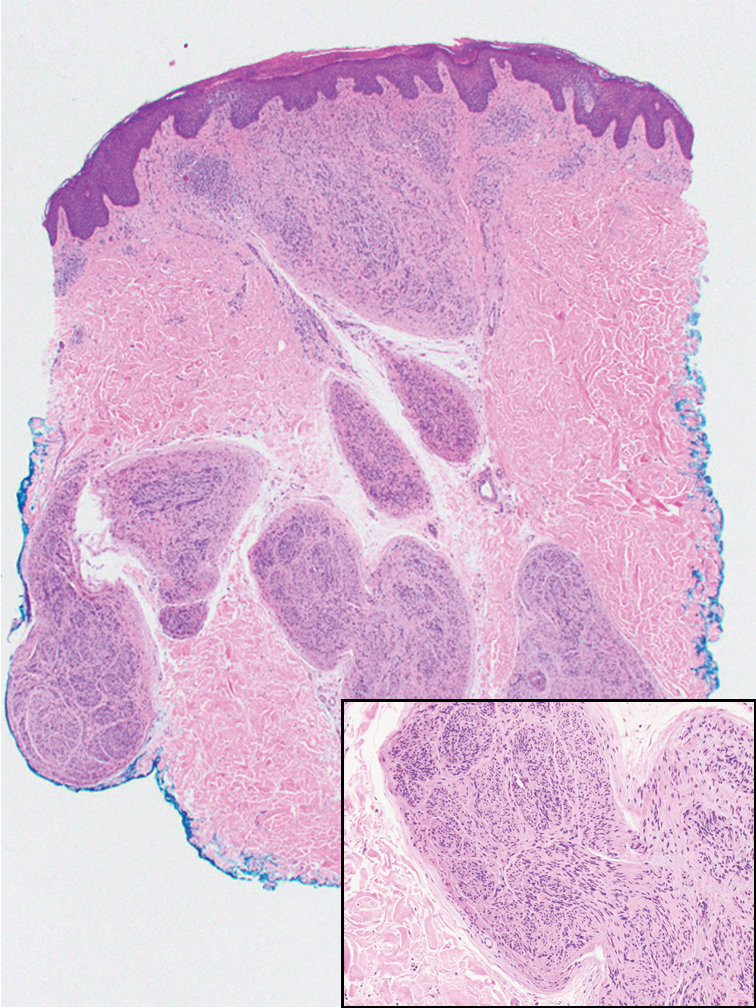

Histopathology revealed poorly circumscribed dermal nodules composed of large pleomorphic and highly atypical basaloid cells as well as increased mitoses. Foci of central necrosis admixed with keratinized cells containing pale eosinophilic cytoplasm and faint nuclear outlines without nuclei also were present. Immunohistochemistry for p63 was positive, while adipophilin, BerEP4, cytokeratin 20, and carcinoembryonic antigen were negative. Tumor cells also demonstrated strong and diffuse nuclear and cytoplasmic β-catenin staining, leading to a diagnosis of pilomatrix carcinoma (PC). The tumor was treated with Mohs micrographic surgery, and the patient was subsequently lost to follow-up.

Pilomatrix carcinoma occurs most often in the fifth through seventh decades of life, with a male-to-female ratio of approximately 1.3:1.1 Due to its rarity, PC management guidelines are not well defined. Histologically, PC will show asymmetry, poor circumscription, and an infiltrative growth pattern at low power. Pilomatrix carcinoma is further characterized by the presence of nodules of atypical basaloid cells demonstrating pleomorphism and nuclear hyperchromatism, increased mitotic index, and the presence of ghost cells (Figure 1).2 Ghost cells are evidence of matrical differentiation. The transition from basaloid to ghost cells may be abrupt. Intralesional calcification is possible but less common.2,3 The tumor nodules can be surrounded by a dense desmoplastic stroma with a predominantly lymphohistiocytic infiltrate.2 Immunohistochemical stains that support a PC diagnosis include lymphoid enhancer-binding factor 1 (LEF1), Ki-67, β-catenin, and p53. Although not specific for malignancy, nuclear LEF1 helps confirm matrical (hair matrix) differentiation.4 Pilomatrix carcinomas show a markedly elevated Ki-67 proliferation marker, reflecting high mitotic activity.5 While benign pilomatricoma may show patchy or minimal p53 staining, PC can demonstrate diffuse strong p53 positivity, consistent with the p53 pathway dysregulation seen in malignant matrical neoplasms.6 Most classically, PC stains strongly positive for nuclear and cytoplasmic β-catenin. Aberrant β-catenin disrupting normal Wnt/β-catenin/Tcf-Lef pathway regulation, which ultimately promotes cellular differentiation and division, is proposed to play a role in tumorigenesis.6,7